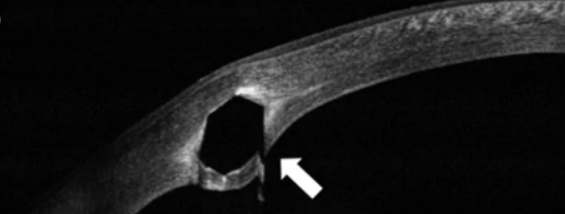

Corneal OCT image of an intrastromal corneal ring segment. This is Intacs model with a hexagonal transverse shape.

Intacs segments have 8.0 mm external diameter and 6.8 mm internal diameter with varied thickness (0.21-0.45 mm, with 0.05-mm increments).